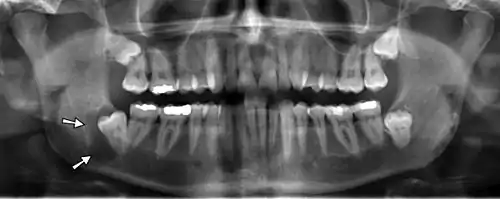

On an x-ray, cysts appear as radiolucent (dark) areas with radiopaque (white) borders. On an x-ray, cysts appear as radiolucent (dark) areas with radiopaque (white) borders in the jaw. [7]However, cysts in maxillary sinus, also known as antrum, can appear radiopaque as the surrounding air absorbs fewer photons than the cystic fluid content.